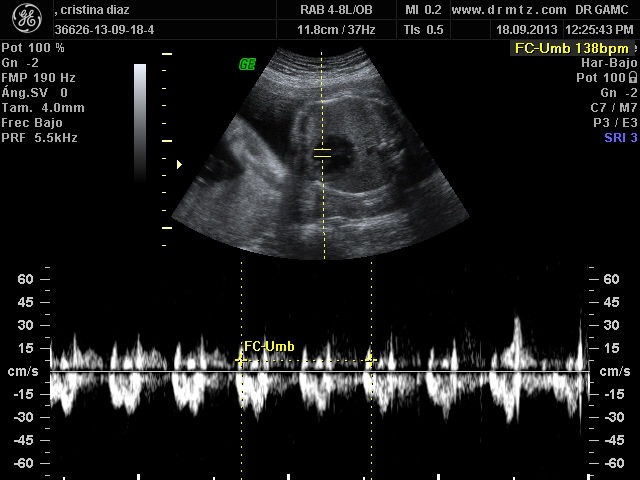

Ginecología . Obstetricia . Medicina Materno Fetal . Ultrasonido 4d HD Live

La consulta de evaluación de riesgos del embarazo tiene como piedra angular una historia clínica detallada, posteriormente la realización de estudios de rutina y finalmente, y de acuerdo con cada caso en particular, estudios especiales (laboratorio, ultrasonidos de nivel II). Al término de estos procedimientos, el médico especialista en ginecología y obstetricia está en la posición de poder establecer si un embarazo es de alto riesgo.